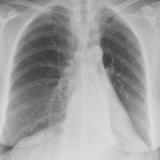

Gallery Lobar Collapse

Lobar Collapse